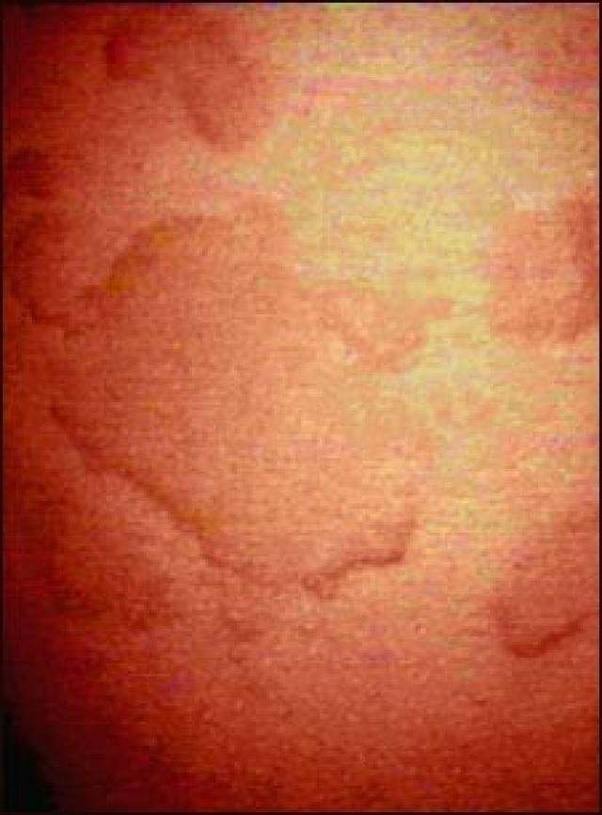

While a flush from a hard run is normal (as is one after falling off the treadmill), all that blood rushing to your face can exacerbate existing skin conditions like rosacea and miliaria (also called sweat rash), making already inflamed skin even worse. The hives, or welts, are large, raised bumps on the skin. While the exact cause of these rashes isn’t necessarily clear, they’re likely linked to a spike in body temperature or an allergy to sweat. Exercise triggers the release of histamines in the body, an inflammatory response to physical exertion or stress which is designed to protect muscles from damage.

This is more likely to happen in warmer months, in warmer climates, and after intense exercise. In hot weather, use air.heat rash occurs when pores become clogged and can’t expel sweat. A heat rash occurs when sweat ducts become blocked causing sweat to become trapped under the skin. But as anyone with an overactive inflammatory response system (eg eczema sufferers!) knows, histamine can cause more problems than it solves, and certainly triggers the dreaded itch.

Common symptoms of heat rash include red bumps on the skin, and a prickly or itchy feeling to the skin (also known as prickly heat). Rashes tend to show up in places where people sweat the most, including the face, neck, under the breasts, the groin or between the thighs — anywhere that's exacerbated by friction. Aside from itching and hives, symptoms may include redness or flushing of the skin, swelling of the face, tongue, and hands, headache, nausea,. If you rule out detergent, soap, or any other lotions, then you should consider a possible allergic reaction during exercise due to the release of histamines. BTS’s V Reveals That He Is Afflicted With Cholinergic Urticaria.